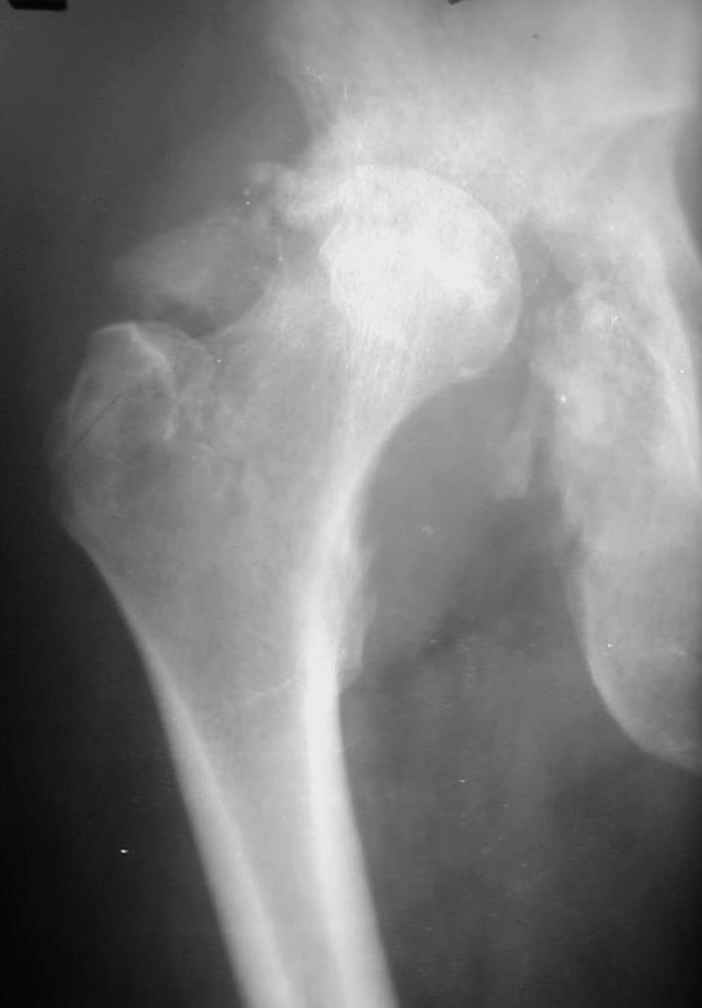

В институте совместно с фирмой Зиммер достаточно регулярно (практически ежемесячно) проводятся 2-х недельные циклы по различным вопросам эндопротезирования. Если есть возможность и желание, мы готовы поделиться с Вами нашим опытом, тем более есть что показать и что обсудить - в настоящее время ежедневно выполняется от 6 до 10 эндопротезирований коленного и тазобедренного сустава. В качестве примеров хочу показать 2 наблюдения, через 1 год и 5 лет после операции

5 лет